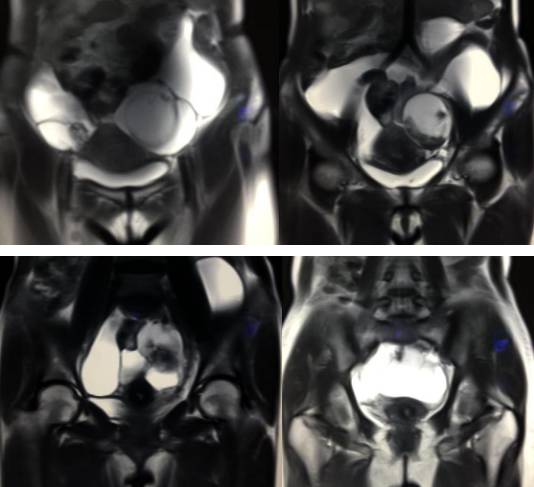

病理结果:黄体血肿

黄体血肿为正常排卵过程中,卵泡层破裂,引起出血,较多的血液潴留在卵泡或黄体腔内形成血肿。

正常黄体直径为15mm左右,以后转变为白体,并在下一个周期的卵泡期自然消退。若黄体内出血量较多,则形成黄体血肿,或称黄体内出血,出血性黄体。黄体血肿多为单侧,一般直径为40mm,偶可达100mm,黄体血肿被吸收后可导致黄体囊肿,较大的血肿破裂时可出现腹腔内出血,剧烈腹痛、少量阴道流血和腹膜刺激征,不易与宫外孕区别。

黄体血肿早期:囊内出血较多时,表现为卵巢内近圆形囊肿,囊壁厚,内壁粗糙。

黄体血肿中期:黄体血肿内血液凝固,部分吸收,囊壁变薄而,内壁光滑。

黄体血肿晚期:血液吸收后囊肿变小,转变为白体,内部回声呈实性稍高回

声,与周围卵巢组织分界不清,面靠彩超显示其周围环状血流判断,当血液完全吸收后形成黄体囊肿,囊壁变得光滑,与卵巢其他囊肿难以区分。

根据时间不同MR信号也有所不同,TIWI脂肪抑制序列可以鉴别脂肪和出血。

卵巢囊肿:呈均匀的T1WI 低信号,T2WI 高信号,边界清楚,壁薄,大多数病灶直径≤5 cm,但囊肿的起源及定性诊断困难。

巧克力囊肿:常呈多发的单囊或多囊改变,病灶大小不等,囊壁厚薄不均,囊内信号复杂,囊内或各囊腔间血液因出血时期不同,信号常呈多样性,囊肿内反复出血、破裂,形成相互粘连的多房性囊肿,是其较为特征性的表现。

在鉴别卵巢畸胎瘤、出血性囊肿或巧克力囊肿时,MR 脂肪抑制T1WI 可明确肿块内高信号成分是脂肪还是出血,同时由于脂肪组织与非脂肪组织的共振频率不同,在两者交界处沿磁场频率编码方向出现化学位移伪影,但出血性囊肿与巧克力囊肿的鉴别有时较为困难。